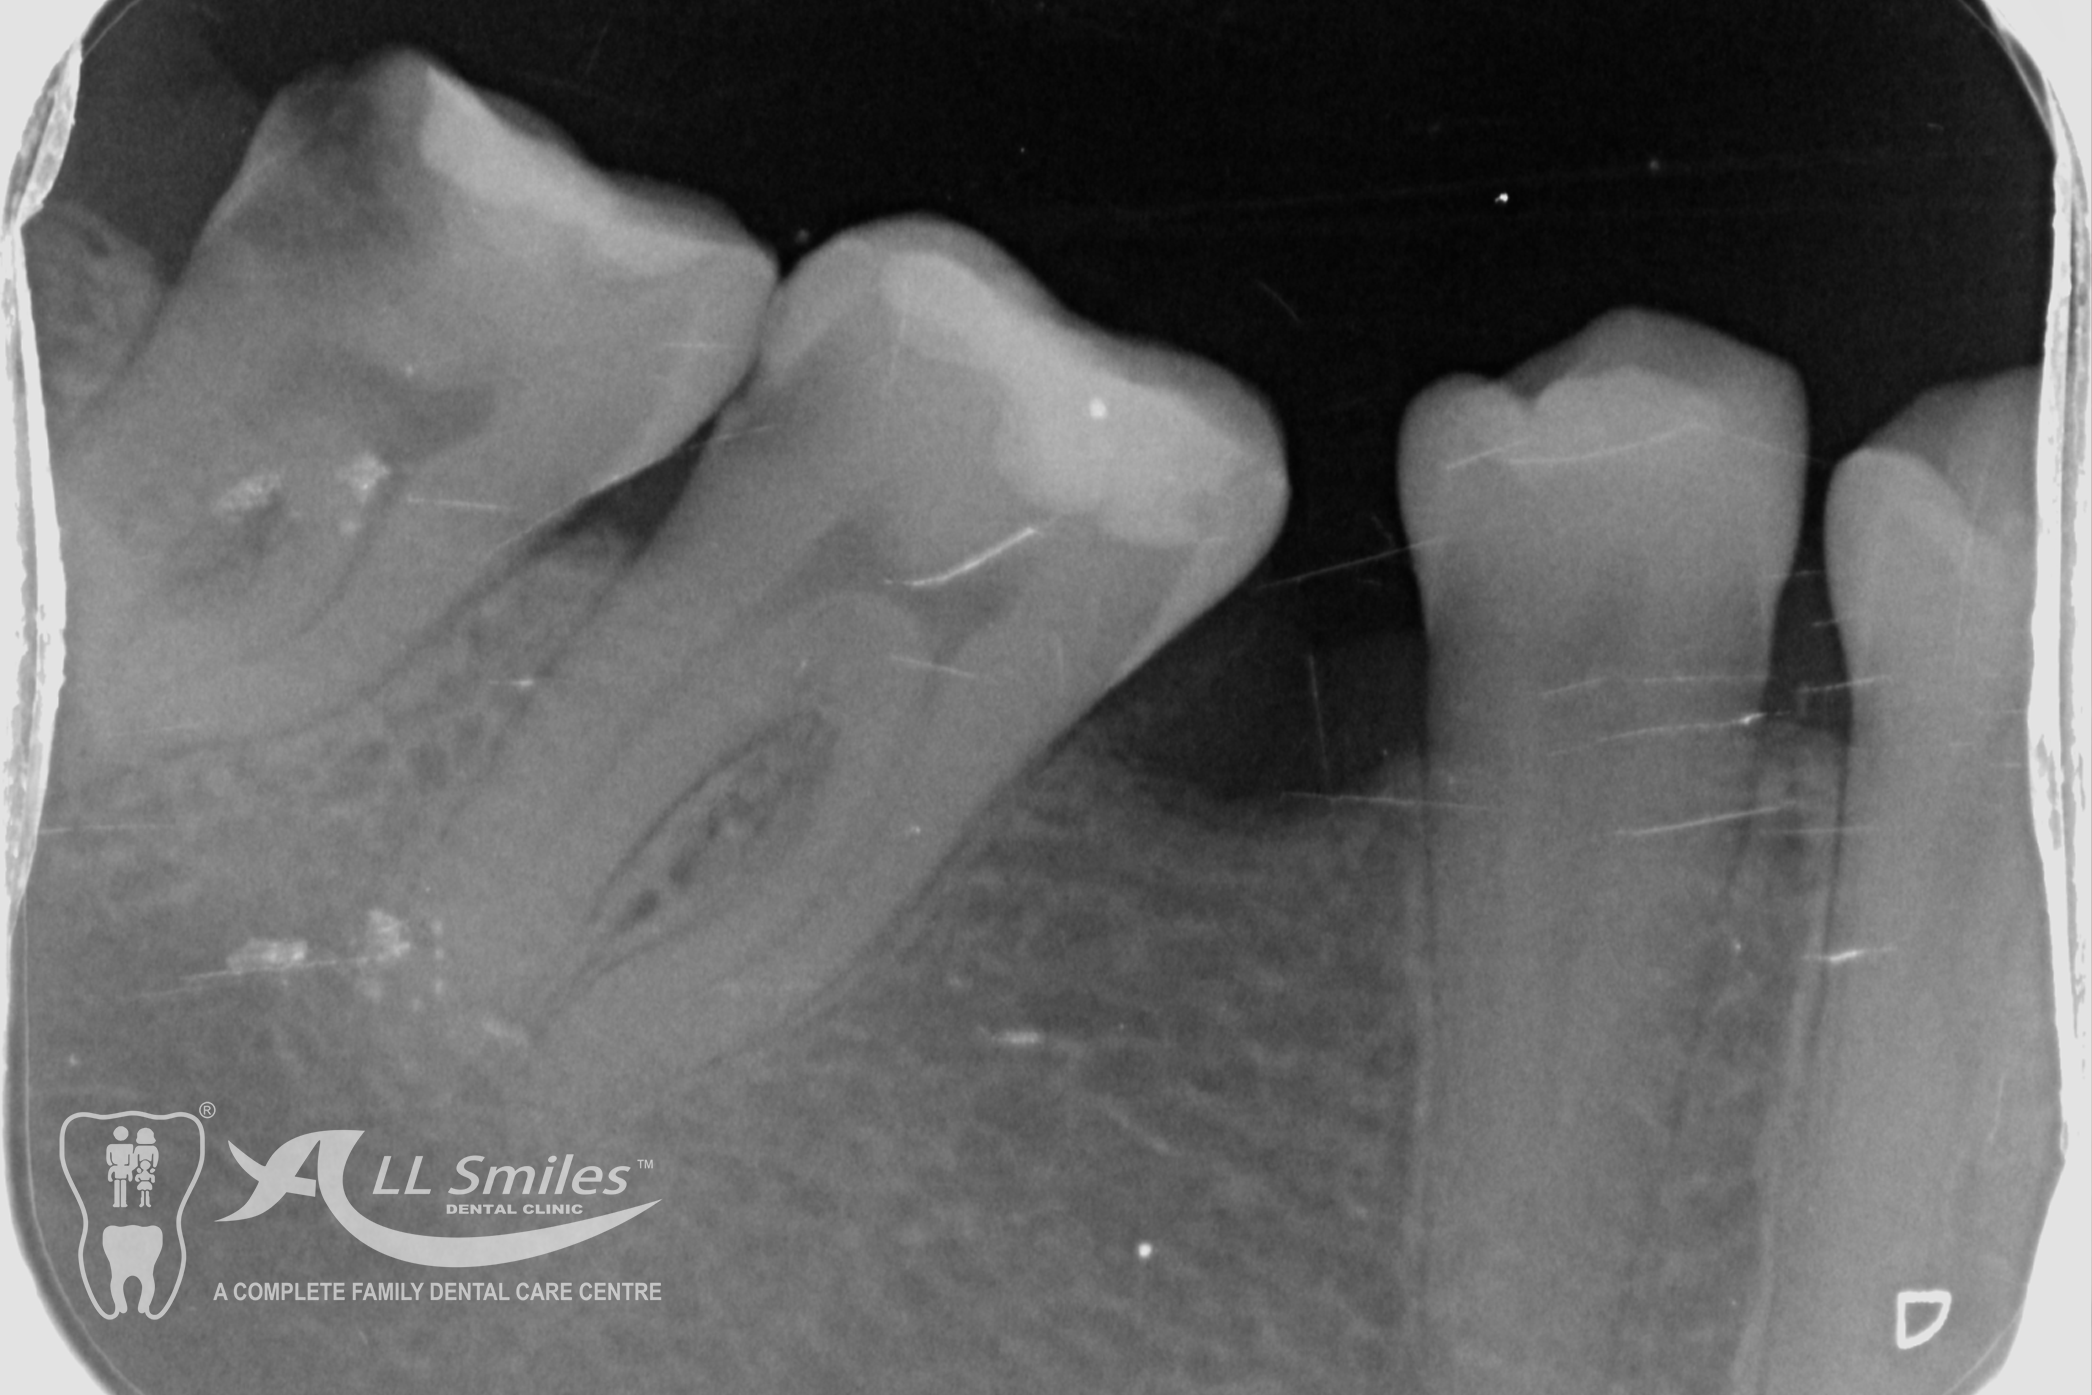

Root Canal Gallery